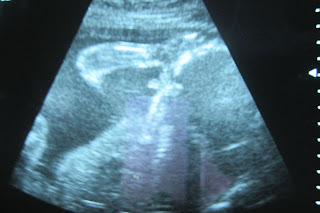

I have to post these because I think they are cuter than me, here is Pumpkin with his hand on his head in our ultrasound last week.

Here is his little leg all stretched out. I love looking at his little foot!

Whit, your belly does look smaller this week! Those are THE best u/s pictures! His little leg stretched out is so cute!